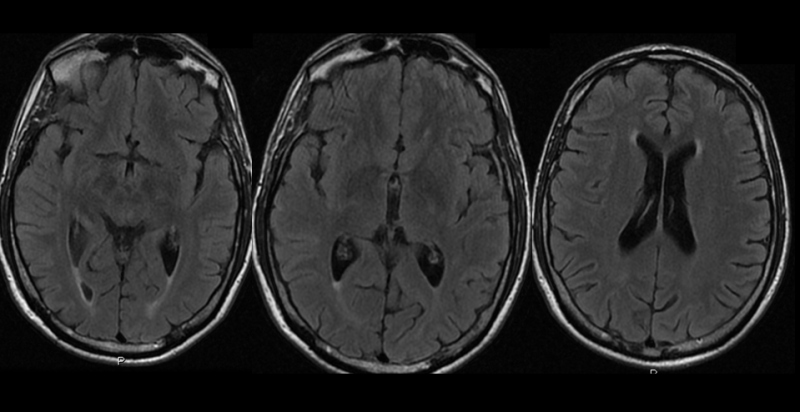

Se realizó PET-RM con 18F-FDG, que evidenció descenso de la actividad neuronal en polo anterior y neocórtex anterolateral de ambos lóbulos temporales, de forma más marcada en el lado derecho, donde se ve comprometido parcialmente el neocórtex póstero-lateral (fig. 2).